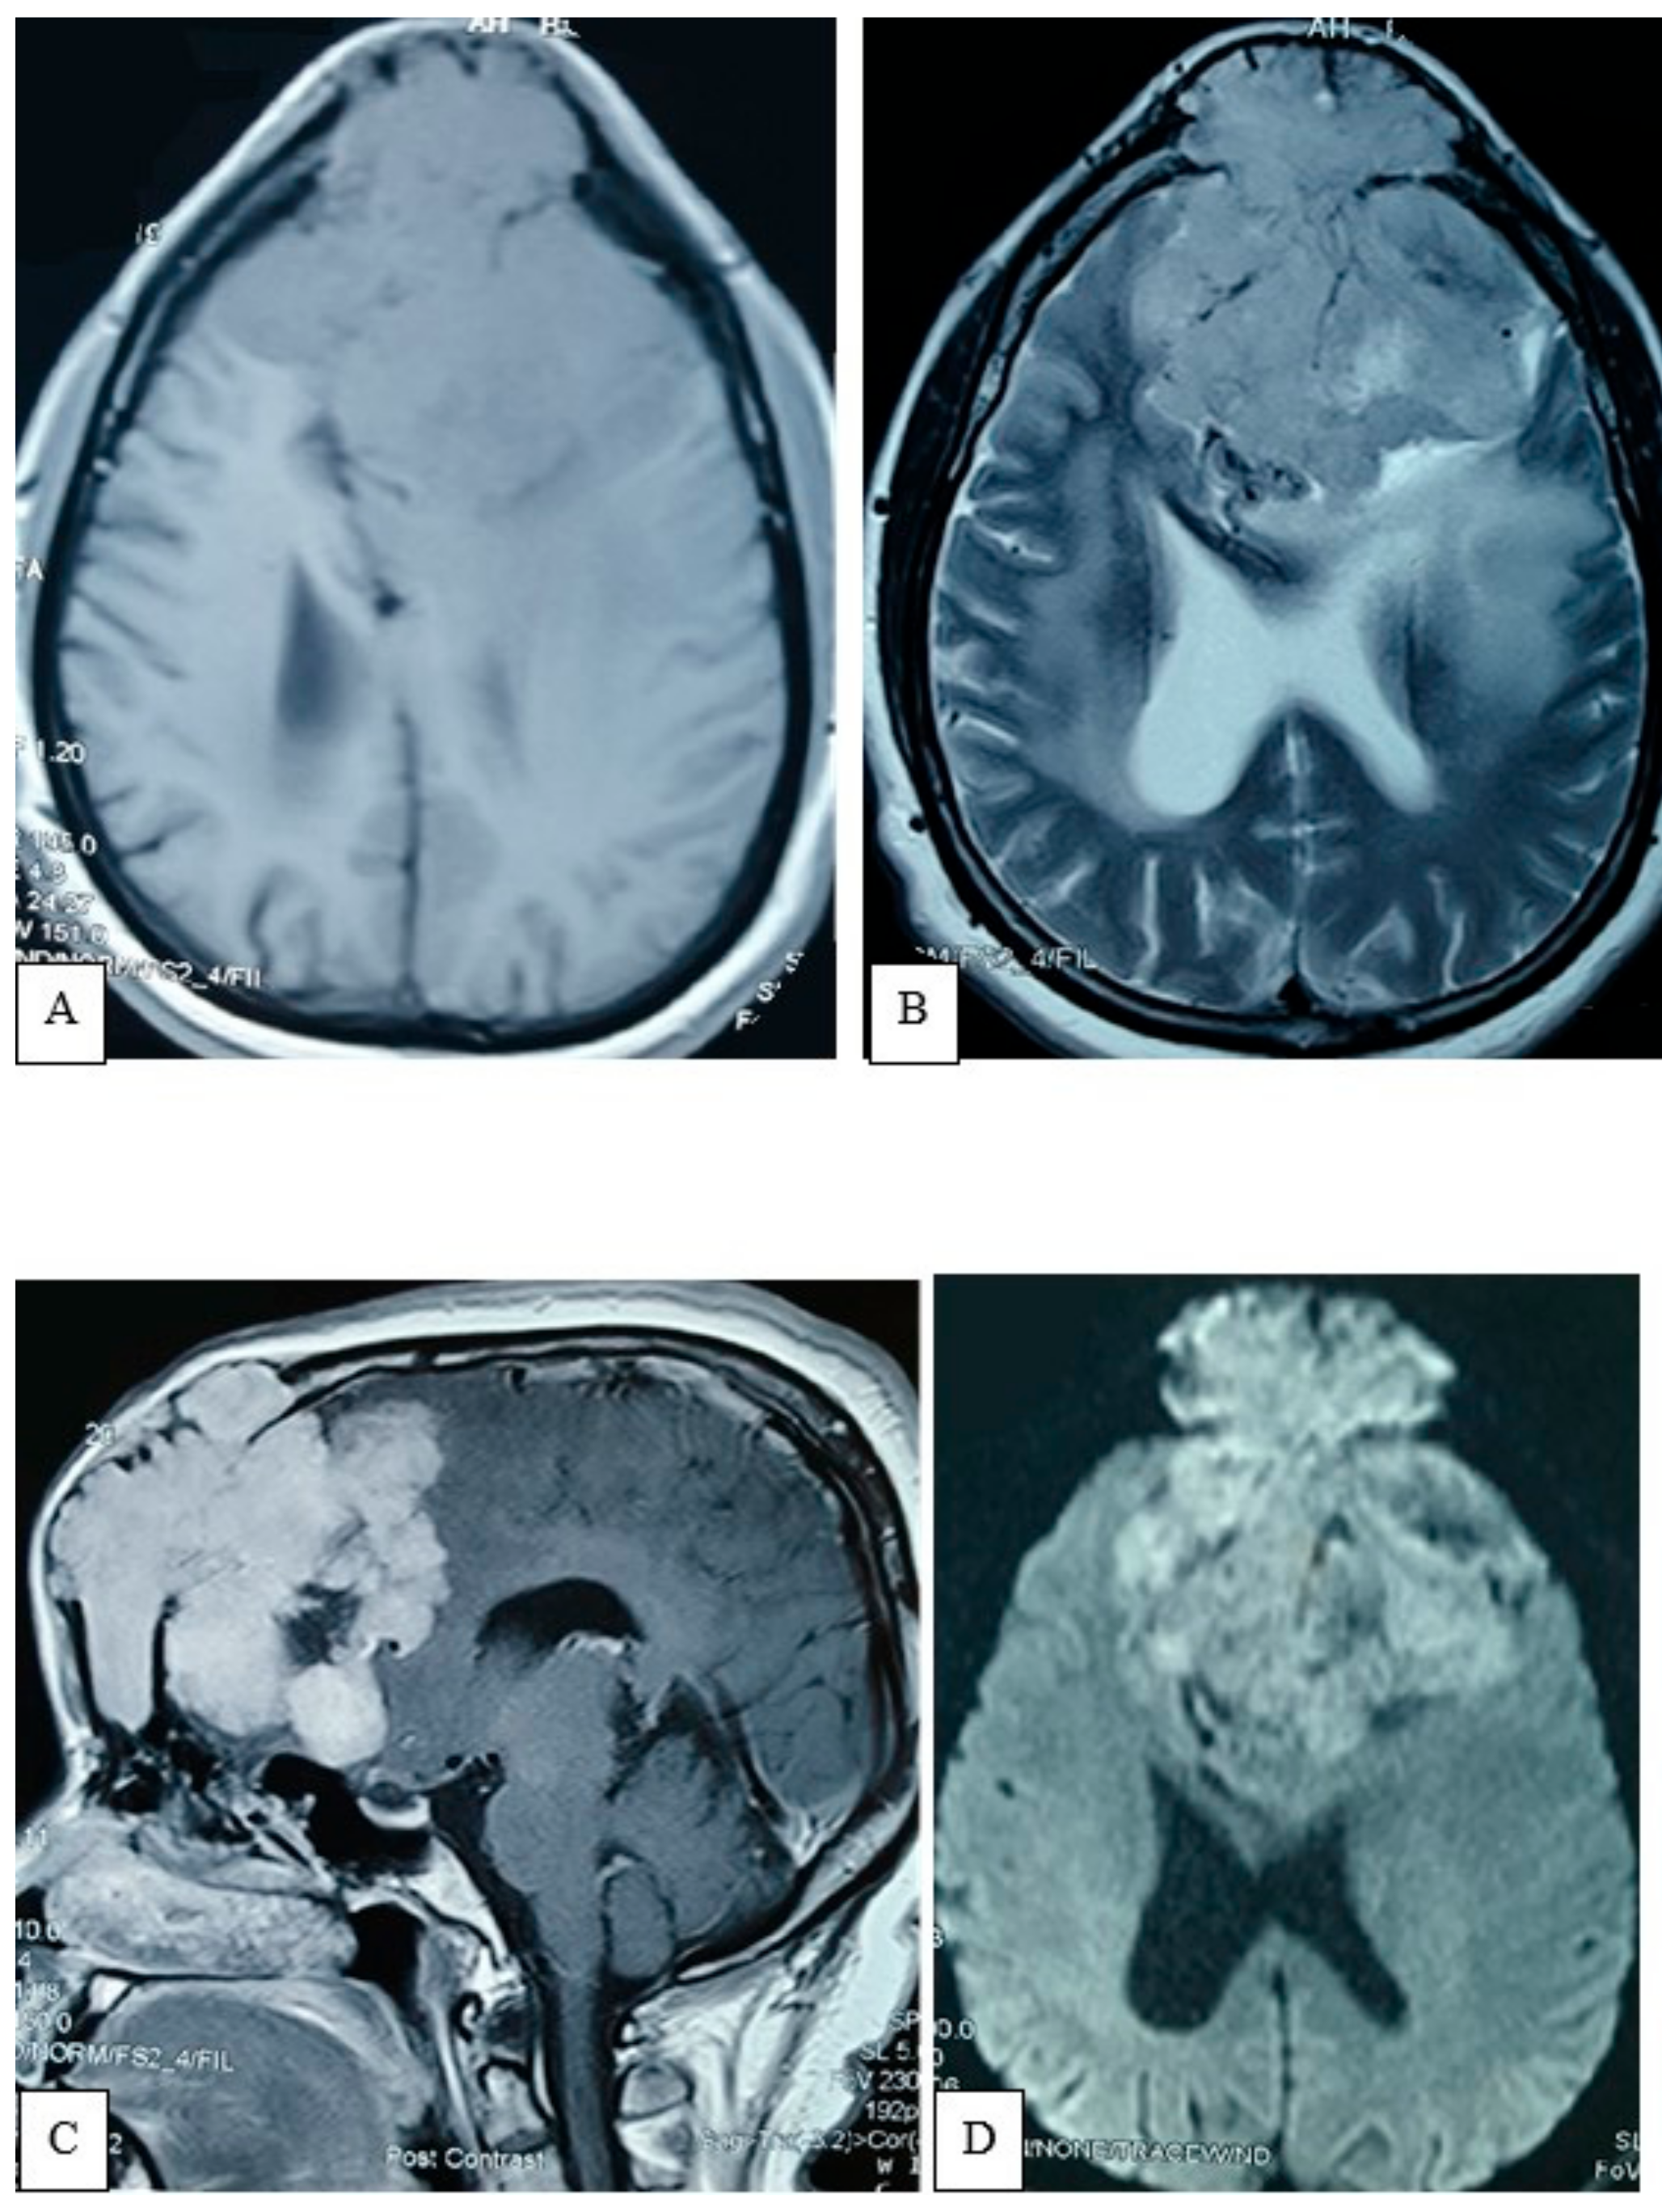

2.4.3. Preoperative Imaging

4.5. Neuroimaging Features and Differential Diagnosis